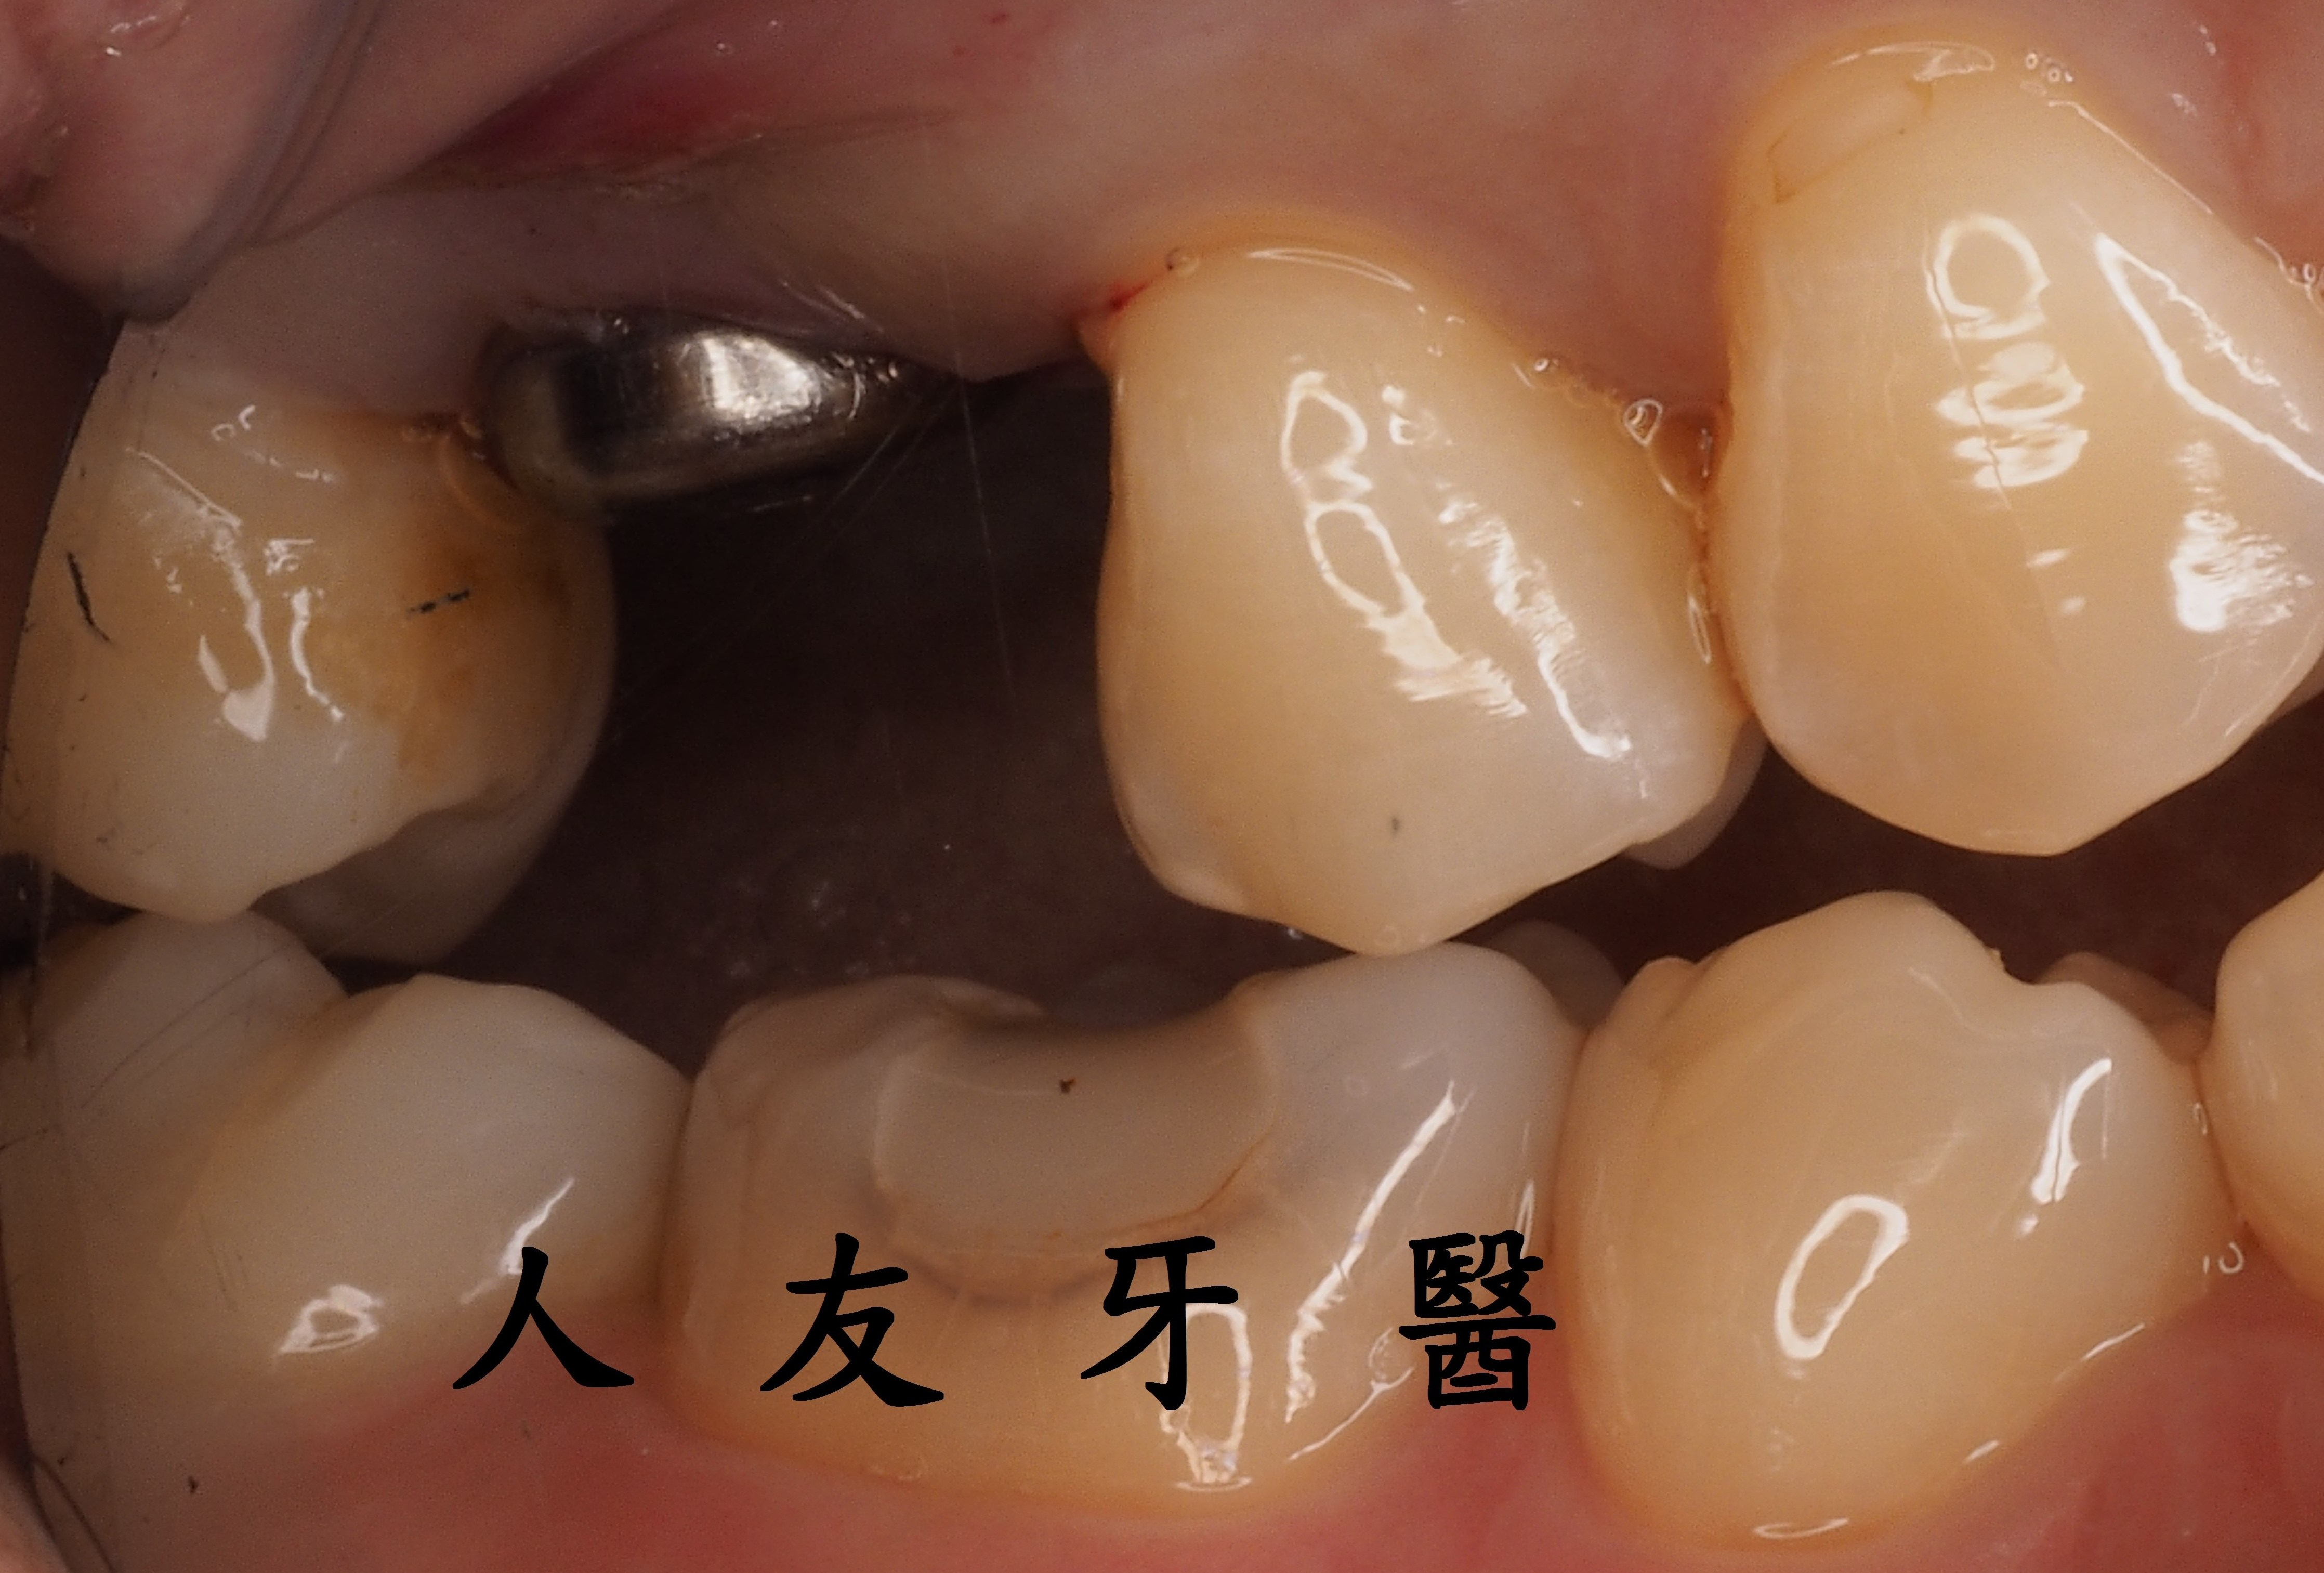

患者蔡先生因牙齒裂到牙根就診,醫師經過 X 光與 CT 電腦斷層評估後確認蔡先生齒槽骨條件合適,可以考慮做現拔現種(植牙)的治療。即是在牙齒拔除的當次診療中,醫師立即將植體植入乾淨的拔牙窩洞裡,讓拔牙傷口與植體一起癒合,除了能縮短治療期程外,也可以少挨一次刀,較快能微創重建缺牙。